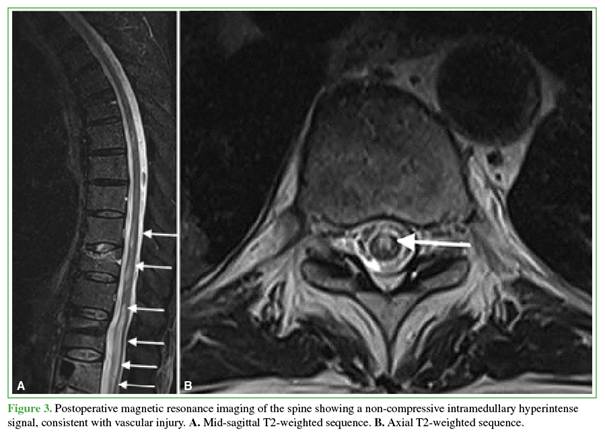

Forty-eight hours after the initial surgery, an emergency spinal magnetic resonance imaging study revealed non-compressive intramedullary hyperintensity consistent with extensive spinal cord ischemia extending from T9 to L4 (Figure 3). The condition was considered a spinal cord injury not amenable to surgical management; therefore, anticoagulation therapy was restarted and the patient was referred to an intensive rehabilitation center.

Hemodynamic compromise: Chronic pericardial effusion limits cardiac reserve.8 Episodes of perioperative hypotension may lead to infarction in spinal cord “watershed zones,” where vascular supply is particularly vulnerable—especially between T4 and T9.6 The image of intramedullary injury, in our case, began at T9.